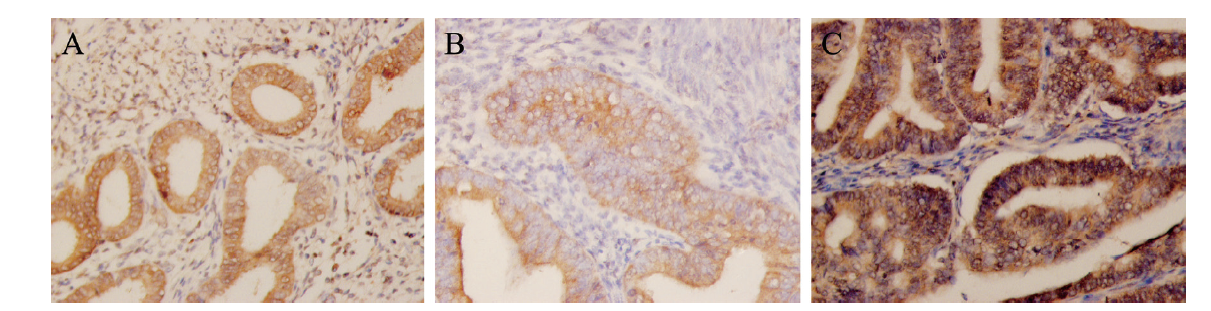

Cyclin D3在正常子宫内膜、单纯型子宫增生内膜和EMC的组织中均呈现阳性表达。其主要在腺细胞或腺癌细胞中表达明显,位于细胞浆中,呈淡黄或棕黄色,基质细胞中呈现阴性表达或弱表达,见图1

图1 不同子宫内膜组织中Cyclin D3的表达

A:正常子宫内膜组织中Cyclin D3的阳性表达(×100);B:单纯型子宫内膜增生组织中Cyclin D3的阳性表达(×200);C:EMC组织中Cyclin D3的阳性表达,主要分布在腺癌细胞胞浆中(×200)

12例正常子宫内膜组织中,有4例为Cyclin D3阳性表达(2例为中表达,2例为高表达),阳性表达率为33%(4/12)。13例单纯型子宫内膜增生组织中,有9例为Cyclin D3阳性表达(6例为中表达,3例为高表达),阳性表达率为69%(9/13)。45例子宫内膜样腺癌组织中,35例为Cyclin D3阳性表达(24例为中表达,11例高表达),阳性表达率为78%(35/45)。Cyclin D3在正常子宫内膜、单纯型子宫内膜增生及子宫内膜样腺癌中的表达比较差异有统计学意义(χ2 = 8.687,P = 0.013),其中子宫内膜样腺癌组高于正常子宫内膜组(χ2 = 8.661,P = 0.003)。